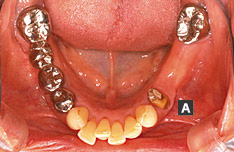

5年程前に歯を抜いてから、ずっと咬みづらく、入れ歯を作ったものの慣れることができませんでした。さらに上の前歯の隙間も開いて、気になるようになってきたとのことで当クリニックを受診されました[A]。

右上、左下の奥歯がないことが咬みづらさの原因と考えられ、まず左下にインプラントを1本埋入しました[B]。

左上前歯の隙間に対しては冠せ物で悩みを解消することにしました。